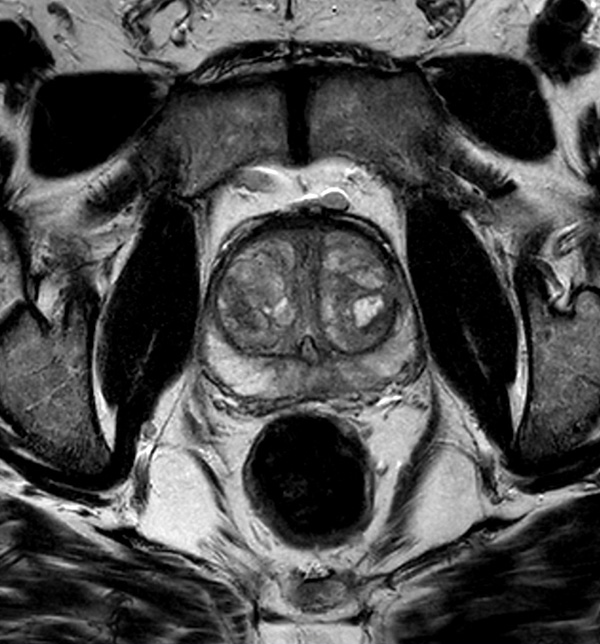

A 60-year-old male with elevated PSA and weak urinary stream underwent MRI. The exam includes high resolution DWI and ADC mapping as well as dynamic imaging. The prostate gland measures 5.2 x 4.4 x 5.9 cm in maximal transverse, AP, and craniocaudal dimensions, respectively, corresponding to an approximate glandular volume of 70 ml. Heterogeneous nodular hypertrophy is seen along the central transitional zone, with hypointense pseudo capsule, indicative of BPH, without dominant T2-hypointense nodules. Patchy T2-hypointense foci are noted throughout the peripheral zone bilaterally at the base, mid-gland and apex, with total PI-RADS score 6, so probably benign. No dominant nodular areas of restricted diffusion are evident. A geographic T2-hyperintense focus in the peripheral zone at the right base to mid-gland, paramidline shows asymmetric restricted diffusion, total PI-RADS score 10. No dominant lesions, greater than 1 cm. Clinical correlation and follow-up are advised.